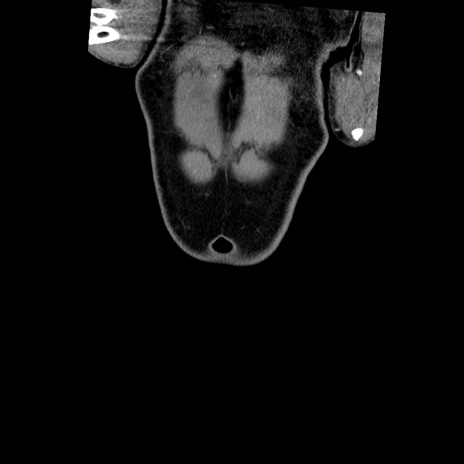

横断像

【症例】50歳代男性

【主訴】腹痛

【現病歴】AVMからの被殻出血のため回復期リハ病棟入院中。 本日午後3時頃急に下腹部痛が出現した。

【既往歴】AVM、被殻出血、虫垂炎、高血圧

【身体所見】意識晴明、左半身不全麻痺、会話の理解は良好、36.5°C、腹部:膨隆、全体に板状硬、下腹部正中に圧痛点あり、反跳痛-、筋性防御不明、右下腹部にope scar

【データ】WBC 9400、CRP 0.06